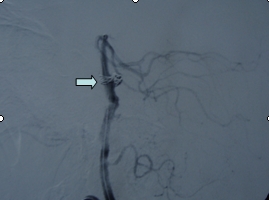

吴某,56岁,因突发昏迷1小时急诊入院。入院时深昏迷,呼吸微弱,血氧和血压降低,双侧瞳孔散大,对光反射迟钝,急诊头颅CT提示蛛网膜下腔出血。入院诊断考虑是脑动脉瘤破裂,紧急行气管插管、止血降颅压等抢救措施,同时放射科陆秀伟主任急诊行全脑血管造影,结果提示基底动脉巨大的动脉瘤(图一)。科主任范学政教授紧急组织全院会诊,组成了包括神经外科、重症医学科、呼吸科、放射科专家抢救小组,采取镇静、脱水、抗血管痉挛以及支持和对症等抢救措施,并病情和影像资料传输到神经外科协助医院四川大学华西医院神经外科远程会诊,会诊认为该病人最佳的治疗方案是行血管内介入治疗。经过充分准备,于入院4日后在华西医院神经外科张昌伟教授联合瑞康医院神经外科医生为患者进行了支架辅助下基底动脉瘤弹簧圈栓塞术,术后行脑血管造影显示动脉瘤完全栓塞(图二)。术后继续予抗血管痉挛等治疗,术后第二天出现呼吸衰竭,肺部感染,后经转入ICU、呼吸科、予以支持、抗感染治疗等综合治疗,术后10天病人清醒,目前患者已经康复出院。

基底动脉瘤